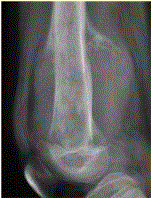

问题 患者男,16岁,左大腿下部疼痛伴肿胀2个月,逐渐加重。自感左膝上方胀痛,尤以夜间为著,伴行走困难。既往史及家族史无特殊。查体:左大腿下部明显肿胀,皮温较对侧升高。碱性磷酸酶明显增高。股骨平片及MRI见下图。 关于此病变的定位,正确的是

选项 A.病变主体位于左股骨下端骨骺,累及干骺端 B.病变主体位于左股骨下端干骺端,累及骨骺 C.病变主体位于左股骨远侧骨端 D.病变主体位于左股骨下端周围软组织,骨质受累 E.病变主体位于骨髓质,皮质受累 F.病变主体位于骨皮质,髓质受累

答案 BE